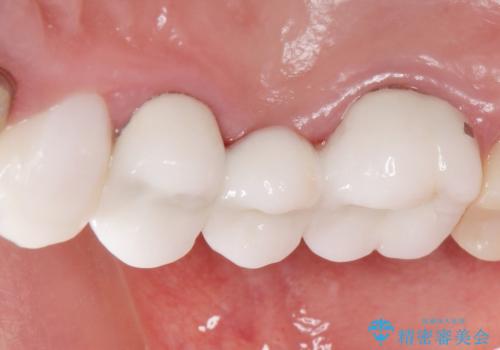

自然な仕上がりと咬み心地に喜んで頂けました。

クラウンの種類:オールセラミッククラウン スタンダード